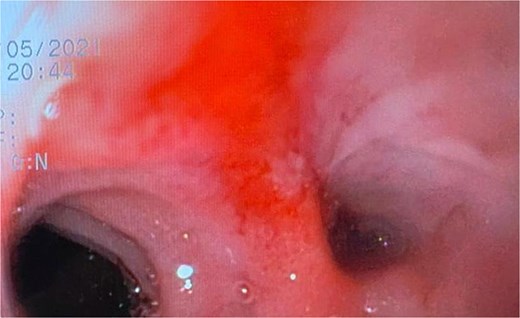

At the last endoscopy 30 days later, 100% granulation tissue was observed with no evidence of a fistulous orifice (Fig. 3). A leak test by fluoroscopy showed no leakage, allowing the initiation of a liquid diet for 15 days, progressing to a normal diet after one month. Follow-up endoscopy showed no pathological findings.

After follow-ups and sponge replacements, the closure of the fistulous defect can be observed.